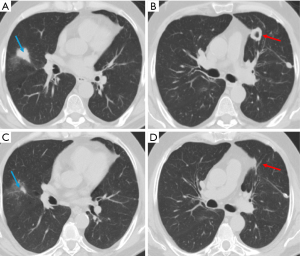

Septic emboli

Septic emboli occur when certain microorganisms cause peripheral pulmonary thrombosis, leading to infarction and microabscesses (7). Major risk factors for septic emboli include immunosuppression, the presence of arterial or intravenous catheters, intravenous drug use, alcoholism, endocarditis, and dental surgery (7,16).

Imaging findings of septic emboli include multiple subpleural, wedge-shaped nodules, which progress into cavities within days (Figure 6) (16). Cavitation is observed in up to 47% of cases on chest X-ray and up to 85% on CT (8). The “feeding vessel” sign, which indicates a distinct vessel leading to the center of the pulmonary nodule, is suggestive of septic emboli (8). Pleural effusion, hilar lymphadenopathy, and mediastinal lymphadenopathy may also be seen (8). The rapid progression of nodules to cavities helps to differentiate them from malignancies (8).